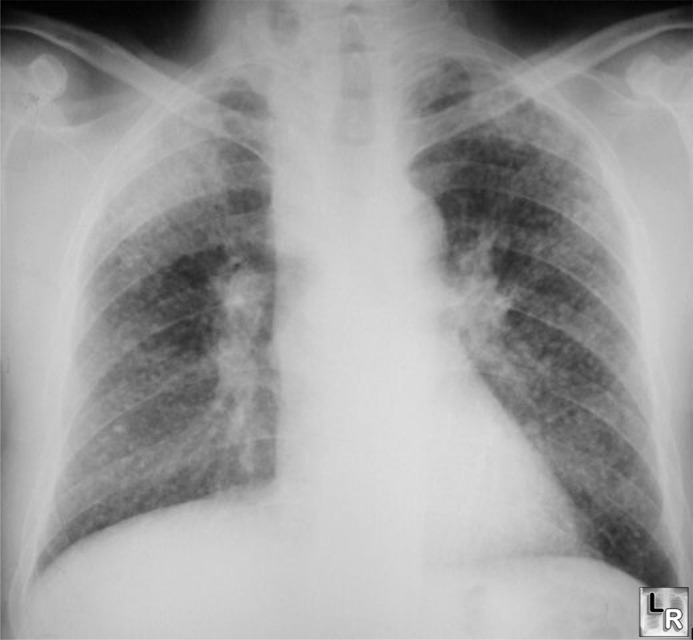

Silica dust in the lungs can take 30 years to turn to silicosis and then more time to, as the doctors say, “metastasize” into cancer – so the operators often died not knowing why. Lots of profit, selling the safety equipment with the bad hole – and very few lawsuits when they don’t. This was particularly true with the Army which didn’t buy the safety equipment. So, because Clark was ordered to operate the “widow maker” from 1971 – 1974, because Ingersoll-Rand made more money selling dangerous pneumatic drills than safe ones, because the Army didn’t care – Clark breathed the deadly silica dust into his pink tender lungs.

The silica dust, sucked into Clark’s lungs, on day-one started to make his nose bleed, to make him cough, and it began to scratch and scar his lungs. When Clark left the service with a life-time cough, he had no idea he was a dead-man walking.

In 2001, the silicosis got so bad Clark fell to his knees coughing violently and broke his ribs. The Army took tissue from his lungs, sent it to Board Certified Pathologist Dr. William Chapman, who found “what was probably silica” in his lungs. Subsequently, cardiothoracic surgeon and author of a medical book on lung diseases, Dr. John Lucke, diagnosed him in April 2001, with the dreaded disease silicosis, and told him his lung had to be taken out.